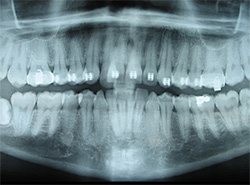

Digital X-Rays

Using the most advanced dental technology possible is just as important as staying up-to-date on the latest treatment techniques. Because our practice is dedicated to providing you with the safest and most convenient treatment options available, we utilize advanced digital X-ray technology in our office.

Digital X-rays provide several advanced imaging options, designed to save time, provide clearer dental photos, and expose patients to less radiation than with traditional X-ray technology.

Our practice is focused on making your dental experience as comfortable as possible. At your next appointment, we’ll be happy to answer any questions you may have.